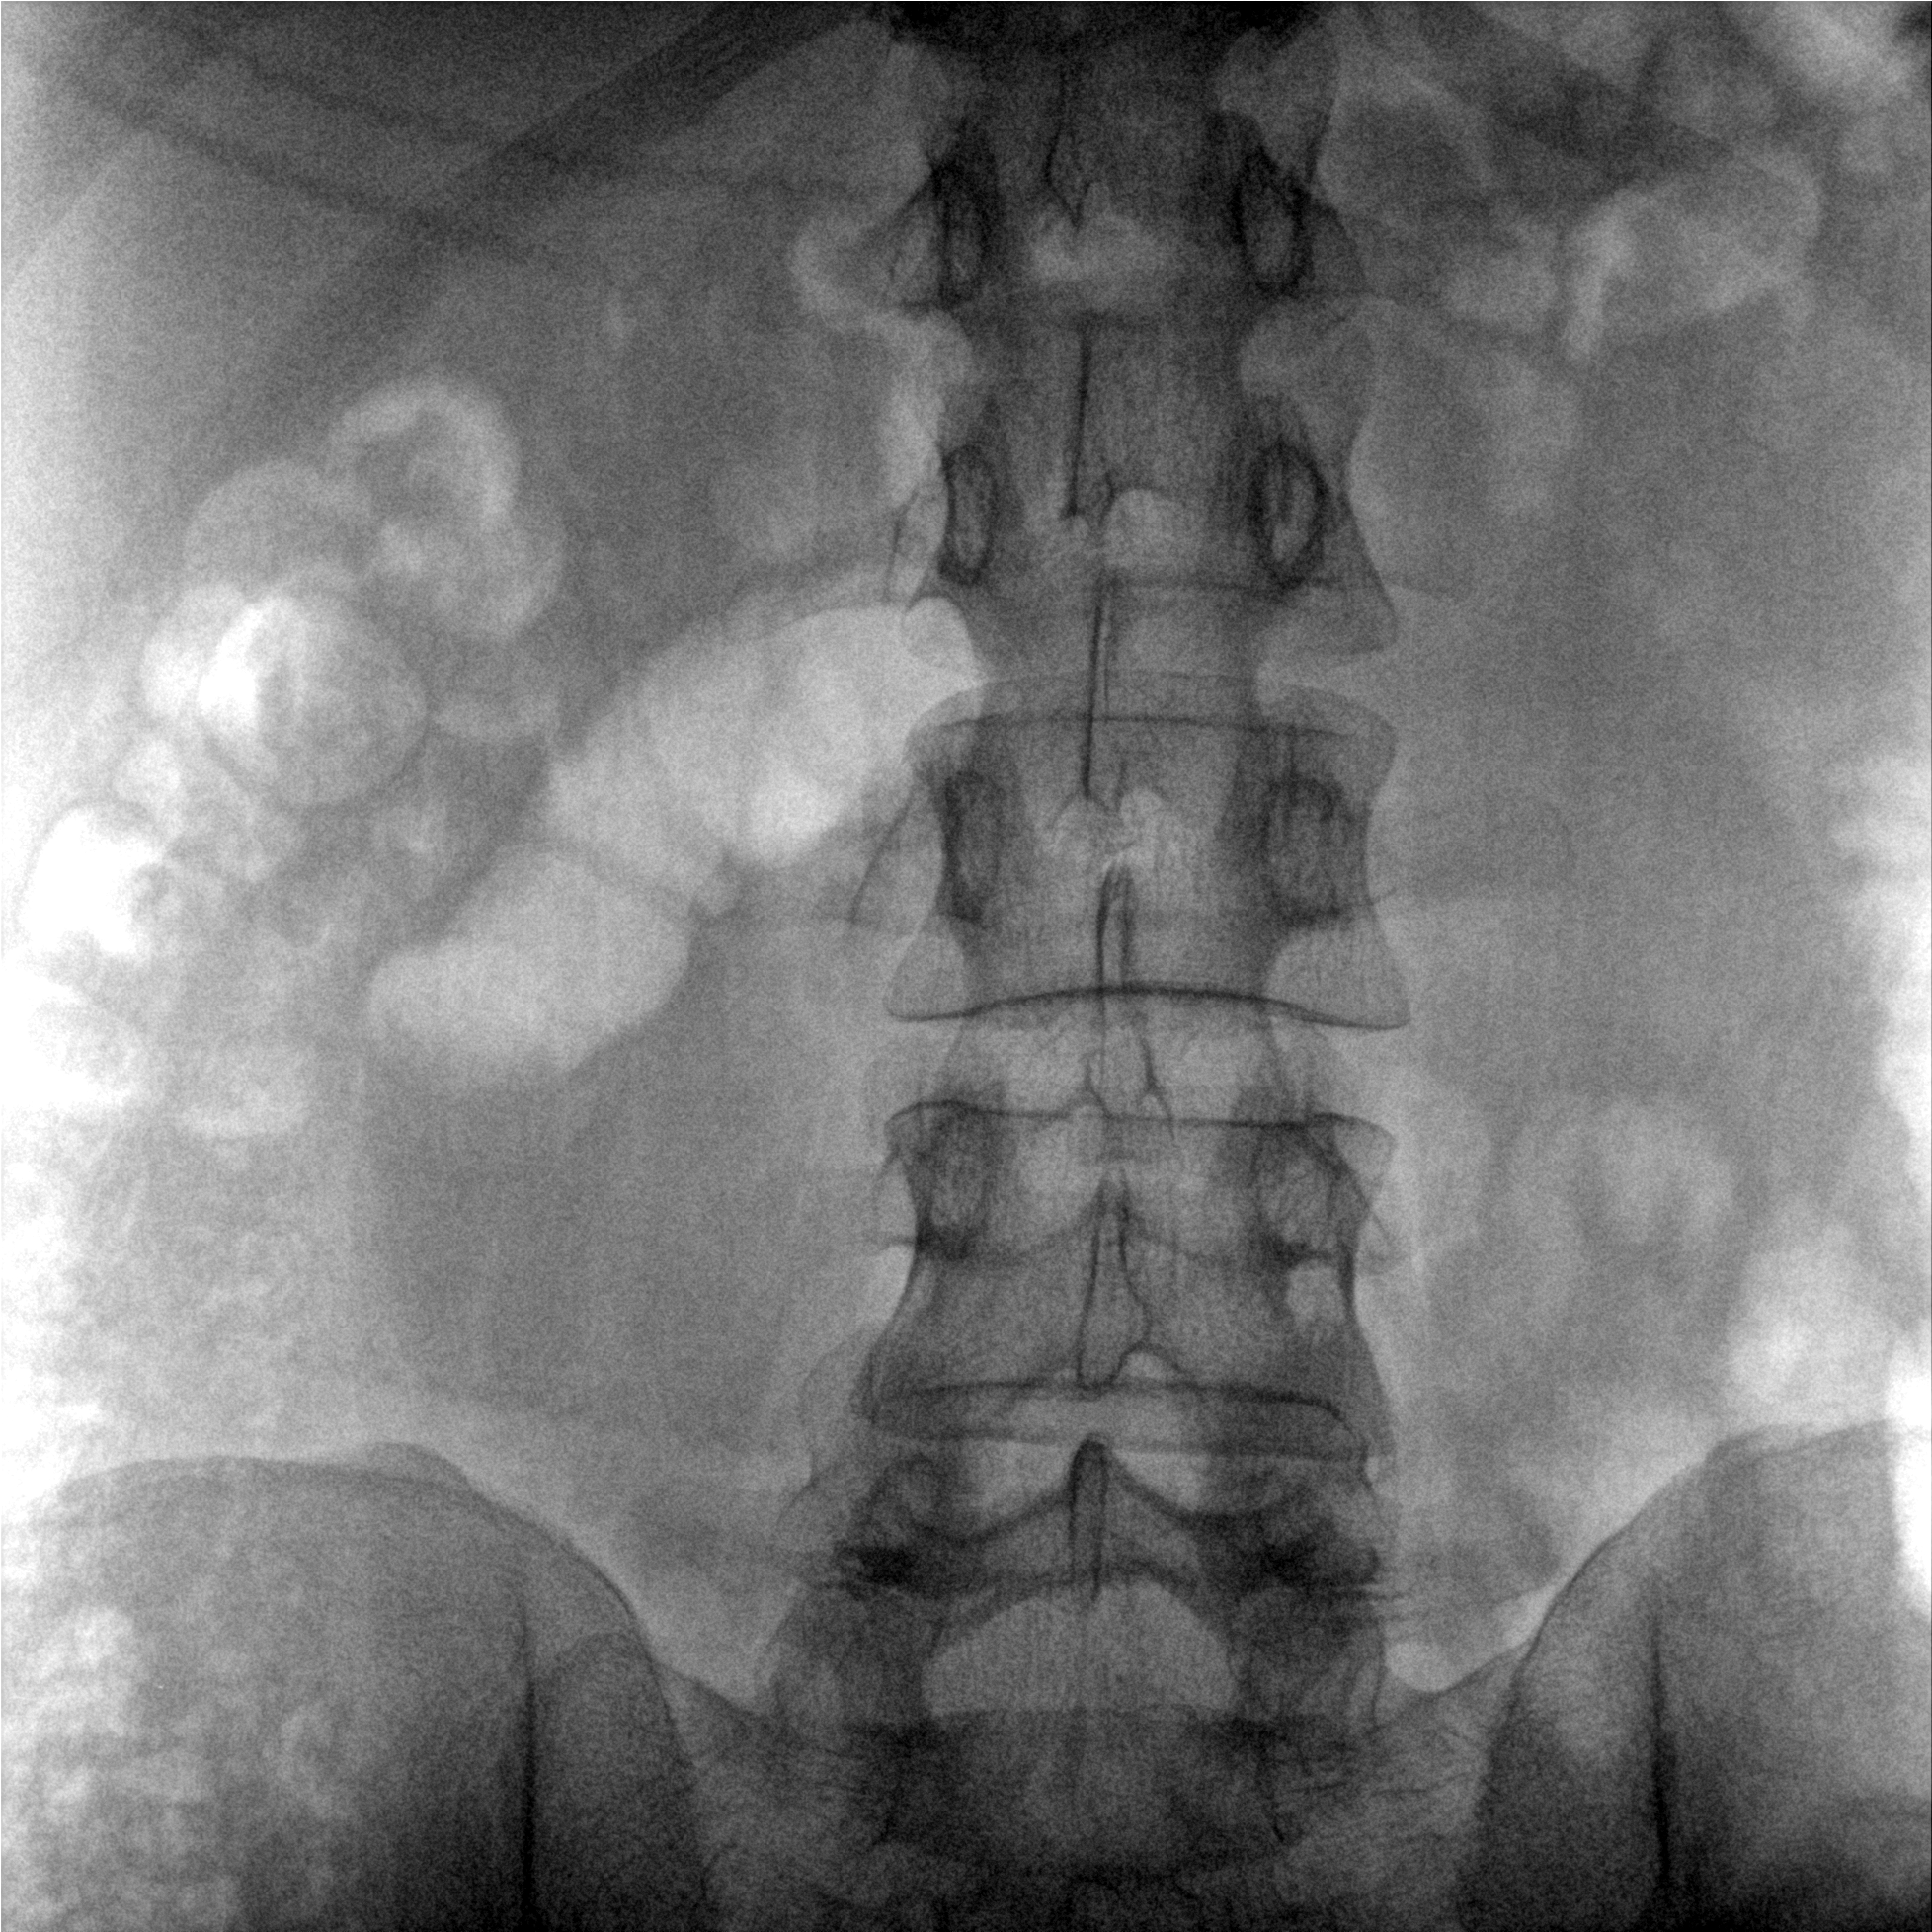

術(shù)中三維成像和橫斷面圖像提供多角度的手術(shù)診斷信息,輔助醫(yī)生進行術(shù)中評估判斷,諸如骨折復位情況和內(nèi)植入螺釘?shù)某叽绾臀恢茫o助手術(shù)更好地完成。

提供更大的術(shù)中三維成像視野,采集更多圖像信息,可一次拍全全段頸椎、全段腰椎、七節(jié)胸椎、雙側(cè)骶髂關(guān)節(jié)、股骨頭及單側(cè)盆骨。